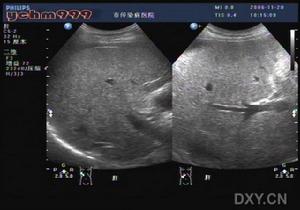

臨床症狀多較輕,有不同程度肝腫大,肝重量常達2000-2500g,甚至達3000g以上(正常1200-1500g)。肝臟色黃,邊緣鈍。鏡下大部分病人的脂變為大泡性脂變,主要見於肝腺泡2、3區分布,嚴重者瀰漫分布。